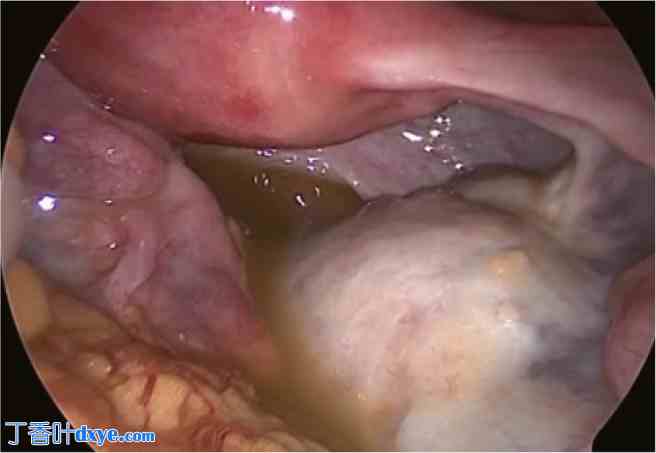

腹腔镜手术前一年的非增强CT扫描。

盆腔中部有一个10厘米长的卵巢畸胎瘤。肿瘤内含有大量脂肪组织和毛球状结构。在同一切片中还观察到另一个3 cm长的畸胎瘤,可能源自右侧卵巢(箭头所示);然而,进行前一个卵巢畸胎瘤切除术的妇科医生并未意识到存在源自对侧卵巢的小畸胎瘤。